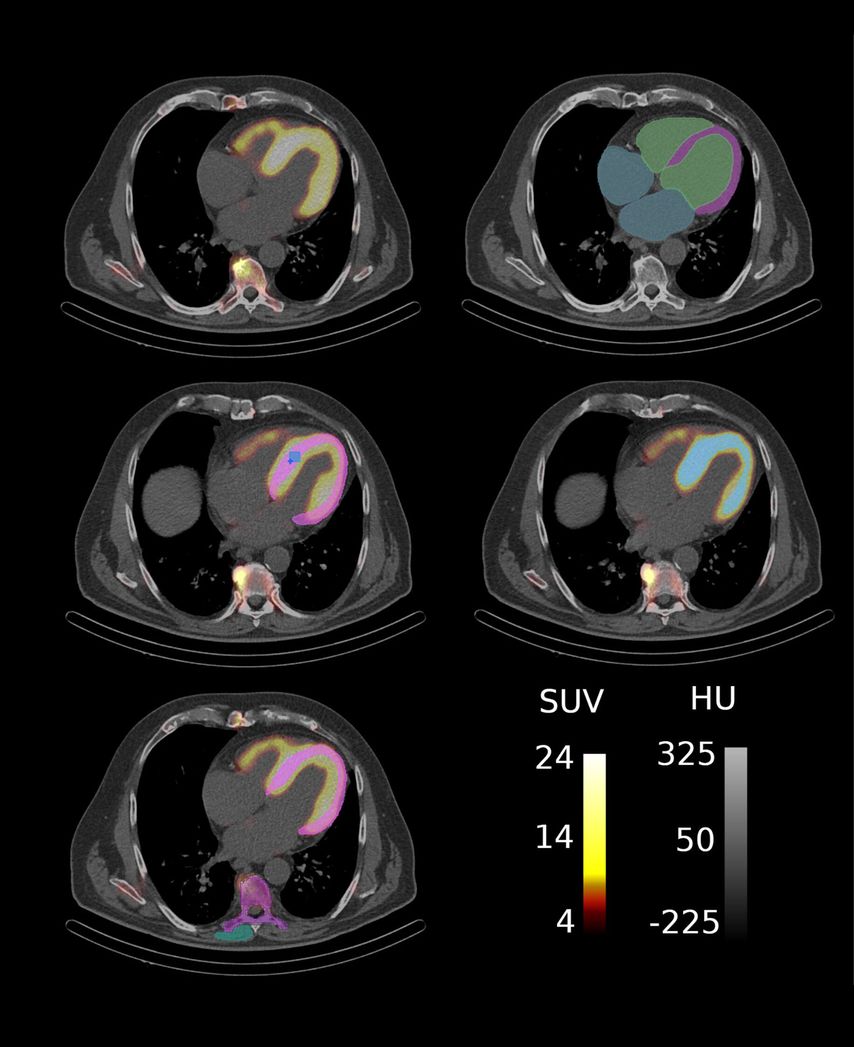

Im Rahmen einer explorativen bildgebenden Studie der Klinischen Abteilung für Kardiologie in Kooperation mit der Klinischen Abteilung für Nuklearmedizin der Medizinischen Universität Wien wurde der Einfluss amyloidspezifischer Therapien auf SPECT/CT-basierte Marker untersucht (Abb. 2), die myokardiale Amyloidablagerungen widerspiegeln. Die KI-gestützte Segmentierung der kardialen Strukturen ermöglicht eine umfassende Quantifizierung der Amyloidablagerungen im Myokard und können als potenzielle nichtinvasive bildgebende Biomarker zur Überwachung der therapeutischen Wirksamkeit bei Patient:innen mit ATTR-CM dienen (Abb. 3).

Abb. 2: ATTR-CM Patient mit Segmentierungsmasken für myokardbasierte Marker: (a) SPECT/CT Aufnahme, (b) CT-Aufnahme mit Basis-Segmentierungen, (c) Segmentierung zur Extraktion klassischer SUV-Parameter wobei SUVpeak in Hellblau und SUVmax in Dunkelblau dargestellt ist, (d) Segmentierung des Amyloid-assoziierten Volumens und (e) Segmentierungen für den Retentionsindex. (Quelle: eigene Anfertigung)